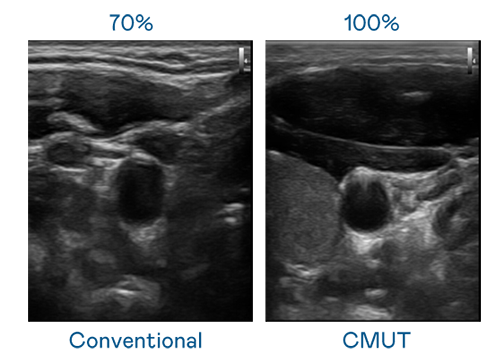

CMUT 技术是一种用电容式微机电元件来产生超音波讯号的技术。与传统 PZT 压电式技术相比,CMUT 频宽增加 30%,更宽频的超音波讯号让影像解析度大幅提升,是实现高影像品质医疗超音波扫描、促进精准医疗发展的关键技术。

大频宽带来超清晰影像

超音波影像的解析度高低,首先取决于探头能发出的讯号频宽。4001百老汇 CMUT 可提供高清晰的超音波讯号,提供高频宽、高灵敏度、影像纹理细节更高的超音波影像,协助医护人员缩短影像判读时间及利用精准的医疗影像进行诊断。